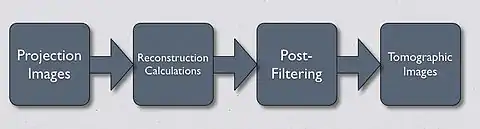

- Image quality can be improved substantially using a modified form of back-projection called Filtered Back Projection (FBP). In this technique - see Figure 7.13 - projection data is first filtered spatially to account for the effect of sudden density changes which cause the streaking in simple back-projection. The filter is referred to as a convolution filter or kernel. The procedure can be performed in the spatial frequency domain using Fourier Transform (FT) methods or directly with spatial domain processing. After the convolution process, the data for each projection is inverse Fourier transformed before the back projection computation is undertaken. In practice the task of image reconstruction is performed using special array processors and dedicated hardware, which aids in speeding up the reconstruction task.

- The overall FBP process is illustrated in the following diagram: